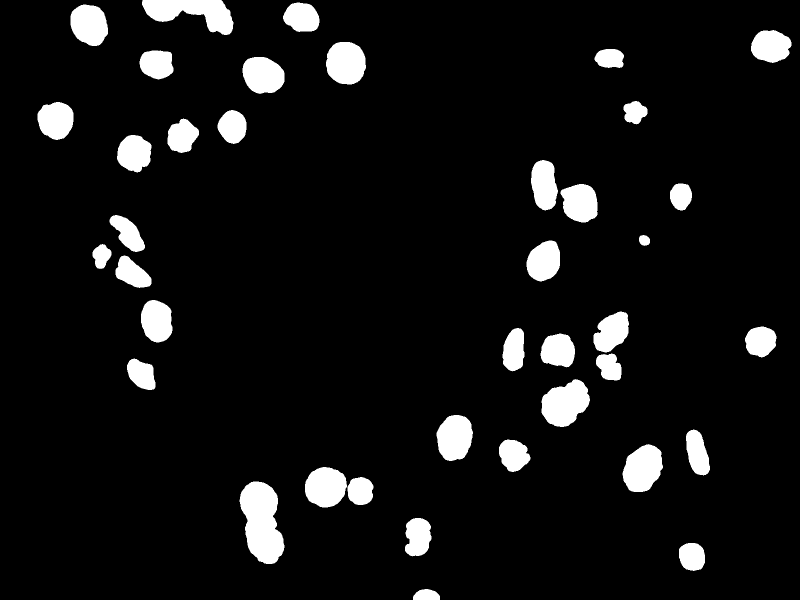

We read the output mask (Fig. 4) from the network and convert it to grayscale (pixel values from 0 to 255). So, a Gaussian Blur with square kernel was applied and then it was performed a threshold operation. Next, we performed an erosion operation and after, an opening (erosion followed by dilation) operation, both with a square kernel. It results in an image similar to the one shown in Fig. 5. This mask is used in the network evaluation process (IoU computation).

Refer to caption

Figure 5. Resulting mask of post-processing step